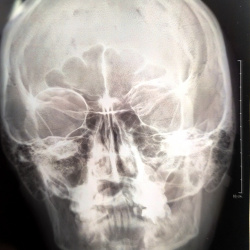

Добрый день. Помогите пожалуйста. слева синусит или образование ? деструкция костной стенки левой ВЧП?